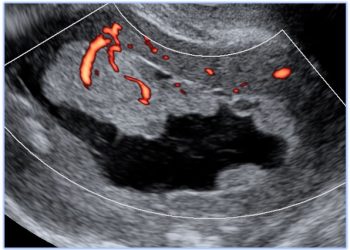

Cari colleghi, vi presentiamo la guida al counseling di Ottobre relativa alla ridotta riserva ovarica e alla conta dei follicoli...